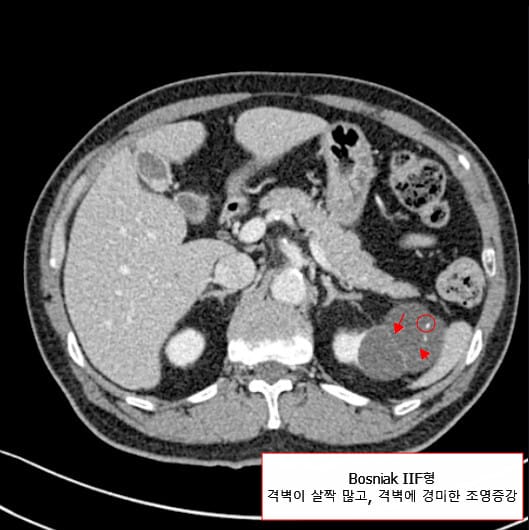

| 🟨 Bosniak ⅡF형 (Follow-up) |

| 격벽이 다소 많거나, 벽/격벽에 경미한 조영증강이 있으나 고형 부위 없음. |

| 악성 위험도 낮지만 완전히 배제되지 않음. 정기적 영상 추적관찰 필요. |